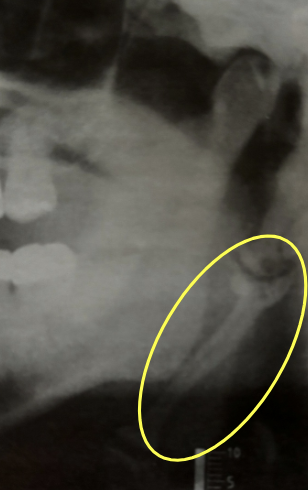

how would you describe this radiographic lesion?

an apical well-defined radiopaque lesion